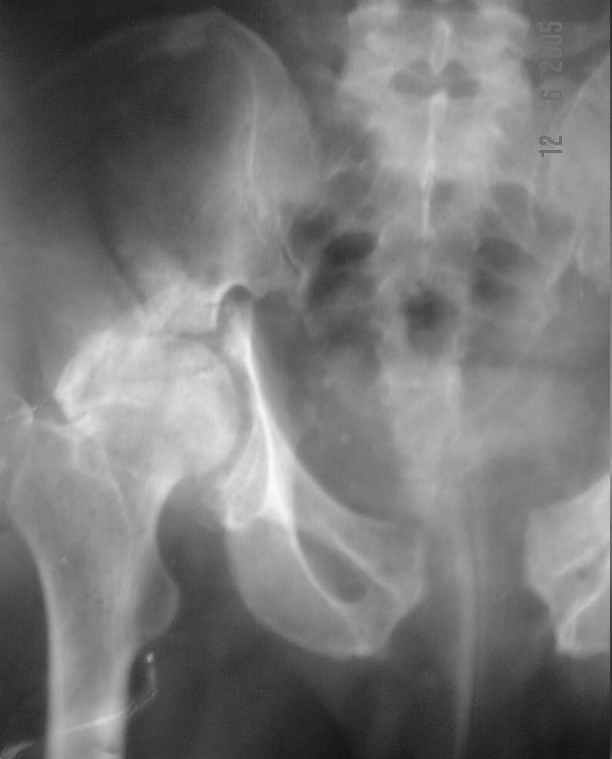

Dear All, The patient came to us for opinion regarding this # of pelvis which he sustained 5 months back.

He gives history of being on skin traction for 3,5months. After that he was advised partial weight bearing to be graduated to full weight bearing. Now the patient has difficulty in weight bearing as it is painful. He can walk a few steps only with the help of a walker. Hip movements are restricted and painful. Fl-90* ER-10* IR-0, shortening-4cm. He also had # of humerus and radius/ulna, which were plated and have united. The serial x-rays of the pelvis/Hip during these 5 months show that the hip joint has been in the same position. I have the CT pictures also but not digitalized as yet.

He is 47 years old, Class-1 officer.What are the options? Expert comments please.1. # Pelvis stabilization - Is it possible at 6 mths? And subsequently THR.

It is a displaced and ununited fracture of the acetabulum, probably type C (AO). The pelvis is not fractured from what one can see of the sacro iliac joint.

Sorry missed the wide open pubic diastasis.